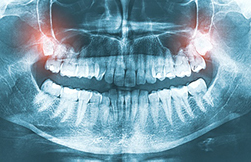

X-ray image of wisdom teeth. Have you ever heard the term "impacted tooth" and wondered what it actually means? Essentially, it describes a tooth that's stuck and unable to erupt fully into its proper position in your mouth. It's like a car stuck in the mud – it's there, but it can't move forward. Let's dive into what causes this and what it means for your oral health.

Several factors can lead to a tooth becoming impacted. Sometimes, there simply isn't enough room in the jaw for all the teeth to fit comfortably. This is especially common with wisdom teeth, which are the last teeth to erupt, usually in our late teens or early twenties. Crowding can block the path of a tooth, preventing it from coming in correctly.

Other times, the tooth might be angled in the wrong direction. Instead of growing straight up, it might be tilted sideways or even lying horizontally. This makes it impossible for the tooth to break through the gum tissue normally. Genetic factors, cysts, or even tumors can also play a role in causing impaction.